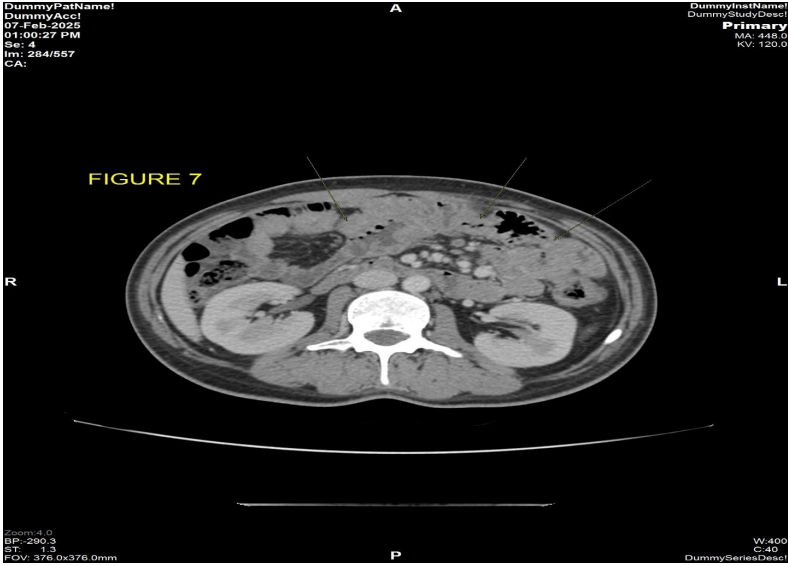

On follow up CECT thorax abdomen pelvis scan (Fig 7) dated 07/02/2025 there is complete resolution of bowel wall thickening and submucosal fat deposition seen involving the jejunal loops with resolution of the symptoms of abdominal pain and diarrhea. [5]

Figure 7: CECT abdomen dated 07/02/2024 axial post contrast view shows complete resolution of the previously seen diffuse circumferential bowel wall thickening with submucosal fat is seen involving the jejunal loops.

Figure 7